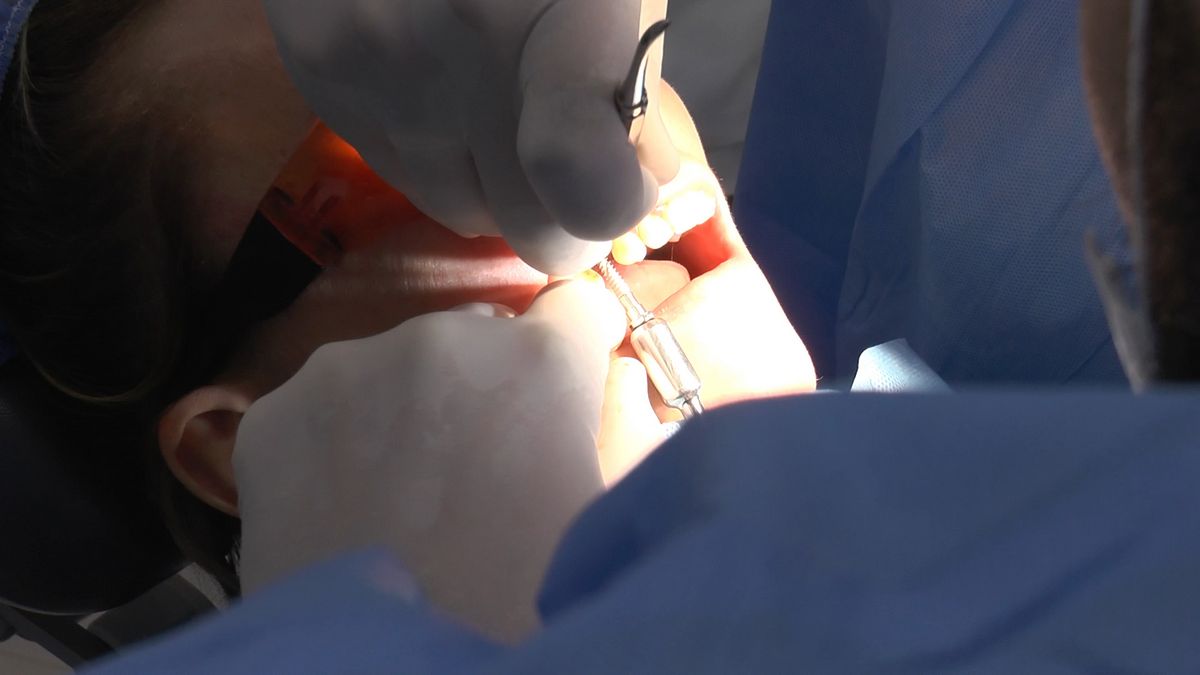

W ostatni weekend czerwca 2018 roku kursanci II Sezonu Preludium Implantologii odbyli piątą, finałową sesję, która w całości podporządkowana była praktyce. W ciągu dwóch dni zabiegowych Lekarze uczestniczący w szkoleniu przeprowadzili szereg zabiegów pod kierunkiem dr n.med. Violetty Szycik. Wszczepili 17 implantów oraz przeprowadzili ekstrakcje i zabiegi regeneracyjne kości. Zabiegi były wykonywane także w sedacji dożylnej z udziałem specjalisty anestezjologii i intensywnej terapii dr Jolanty Grzybowskiej. Preludium implantologii to nowy program edukacyjny dla adeptów implantologii stomatologicznej, którego celem jest wprowadzenie do implantologii poprzez pozyskanie wiedzy w szerokim zakresie i uwzględnieniem szczegółów mających decydujące znaczenie dla powodzenia leczenia implantologicznego. Ale tak jak wszystkie szkolenia w Instytucie Vivadental, w tym wiodące Practiculum Implantologii, zorientowane jest na praktyce i samodzielnym wykonywaniu zabiegów pod kierunkiem Mentora. To najlepsza edukacja w medycynie zabiegowej, a zarazem najlepszy start do implantologii.